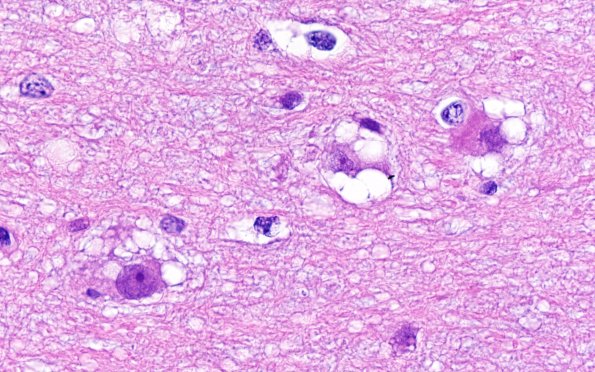

Washington University Experience | NEOPLASMS (NEURONAL) | Multinodular Vacuolating Neuronal Tumor | 3B12MVNT (Case 3) H&E 100X 8

Astrocytes have a gemistocytic or fibrillary appearance in these high magnification images. The vacuolation of these neurons remind me of the olivary hyperplasia alteration sometimes designated “mulberry-like”. (H&E)